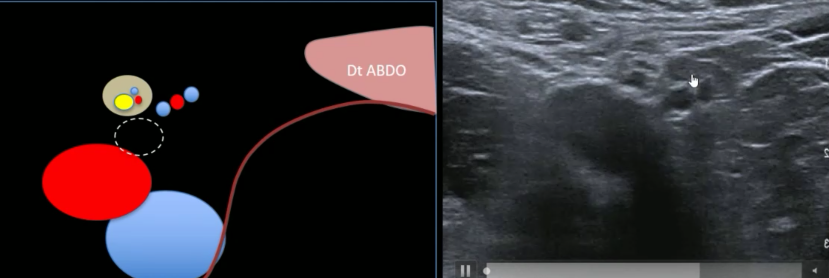

Hernie inguinale indirecte

Hernie inguinale directe

Coupe sagittale

- Confirme l’hernie

- Mesure le collet